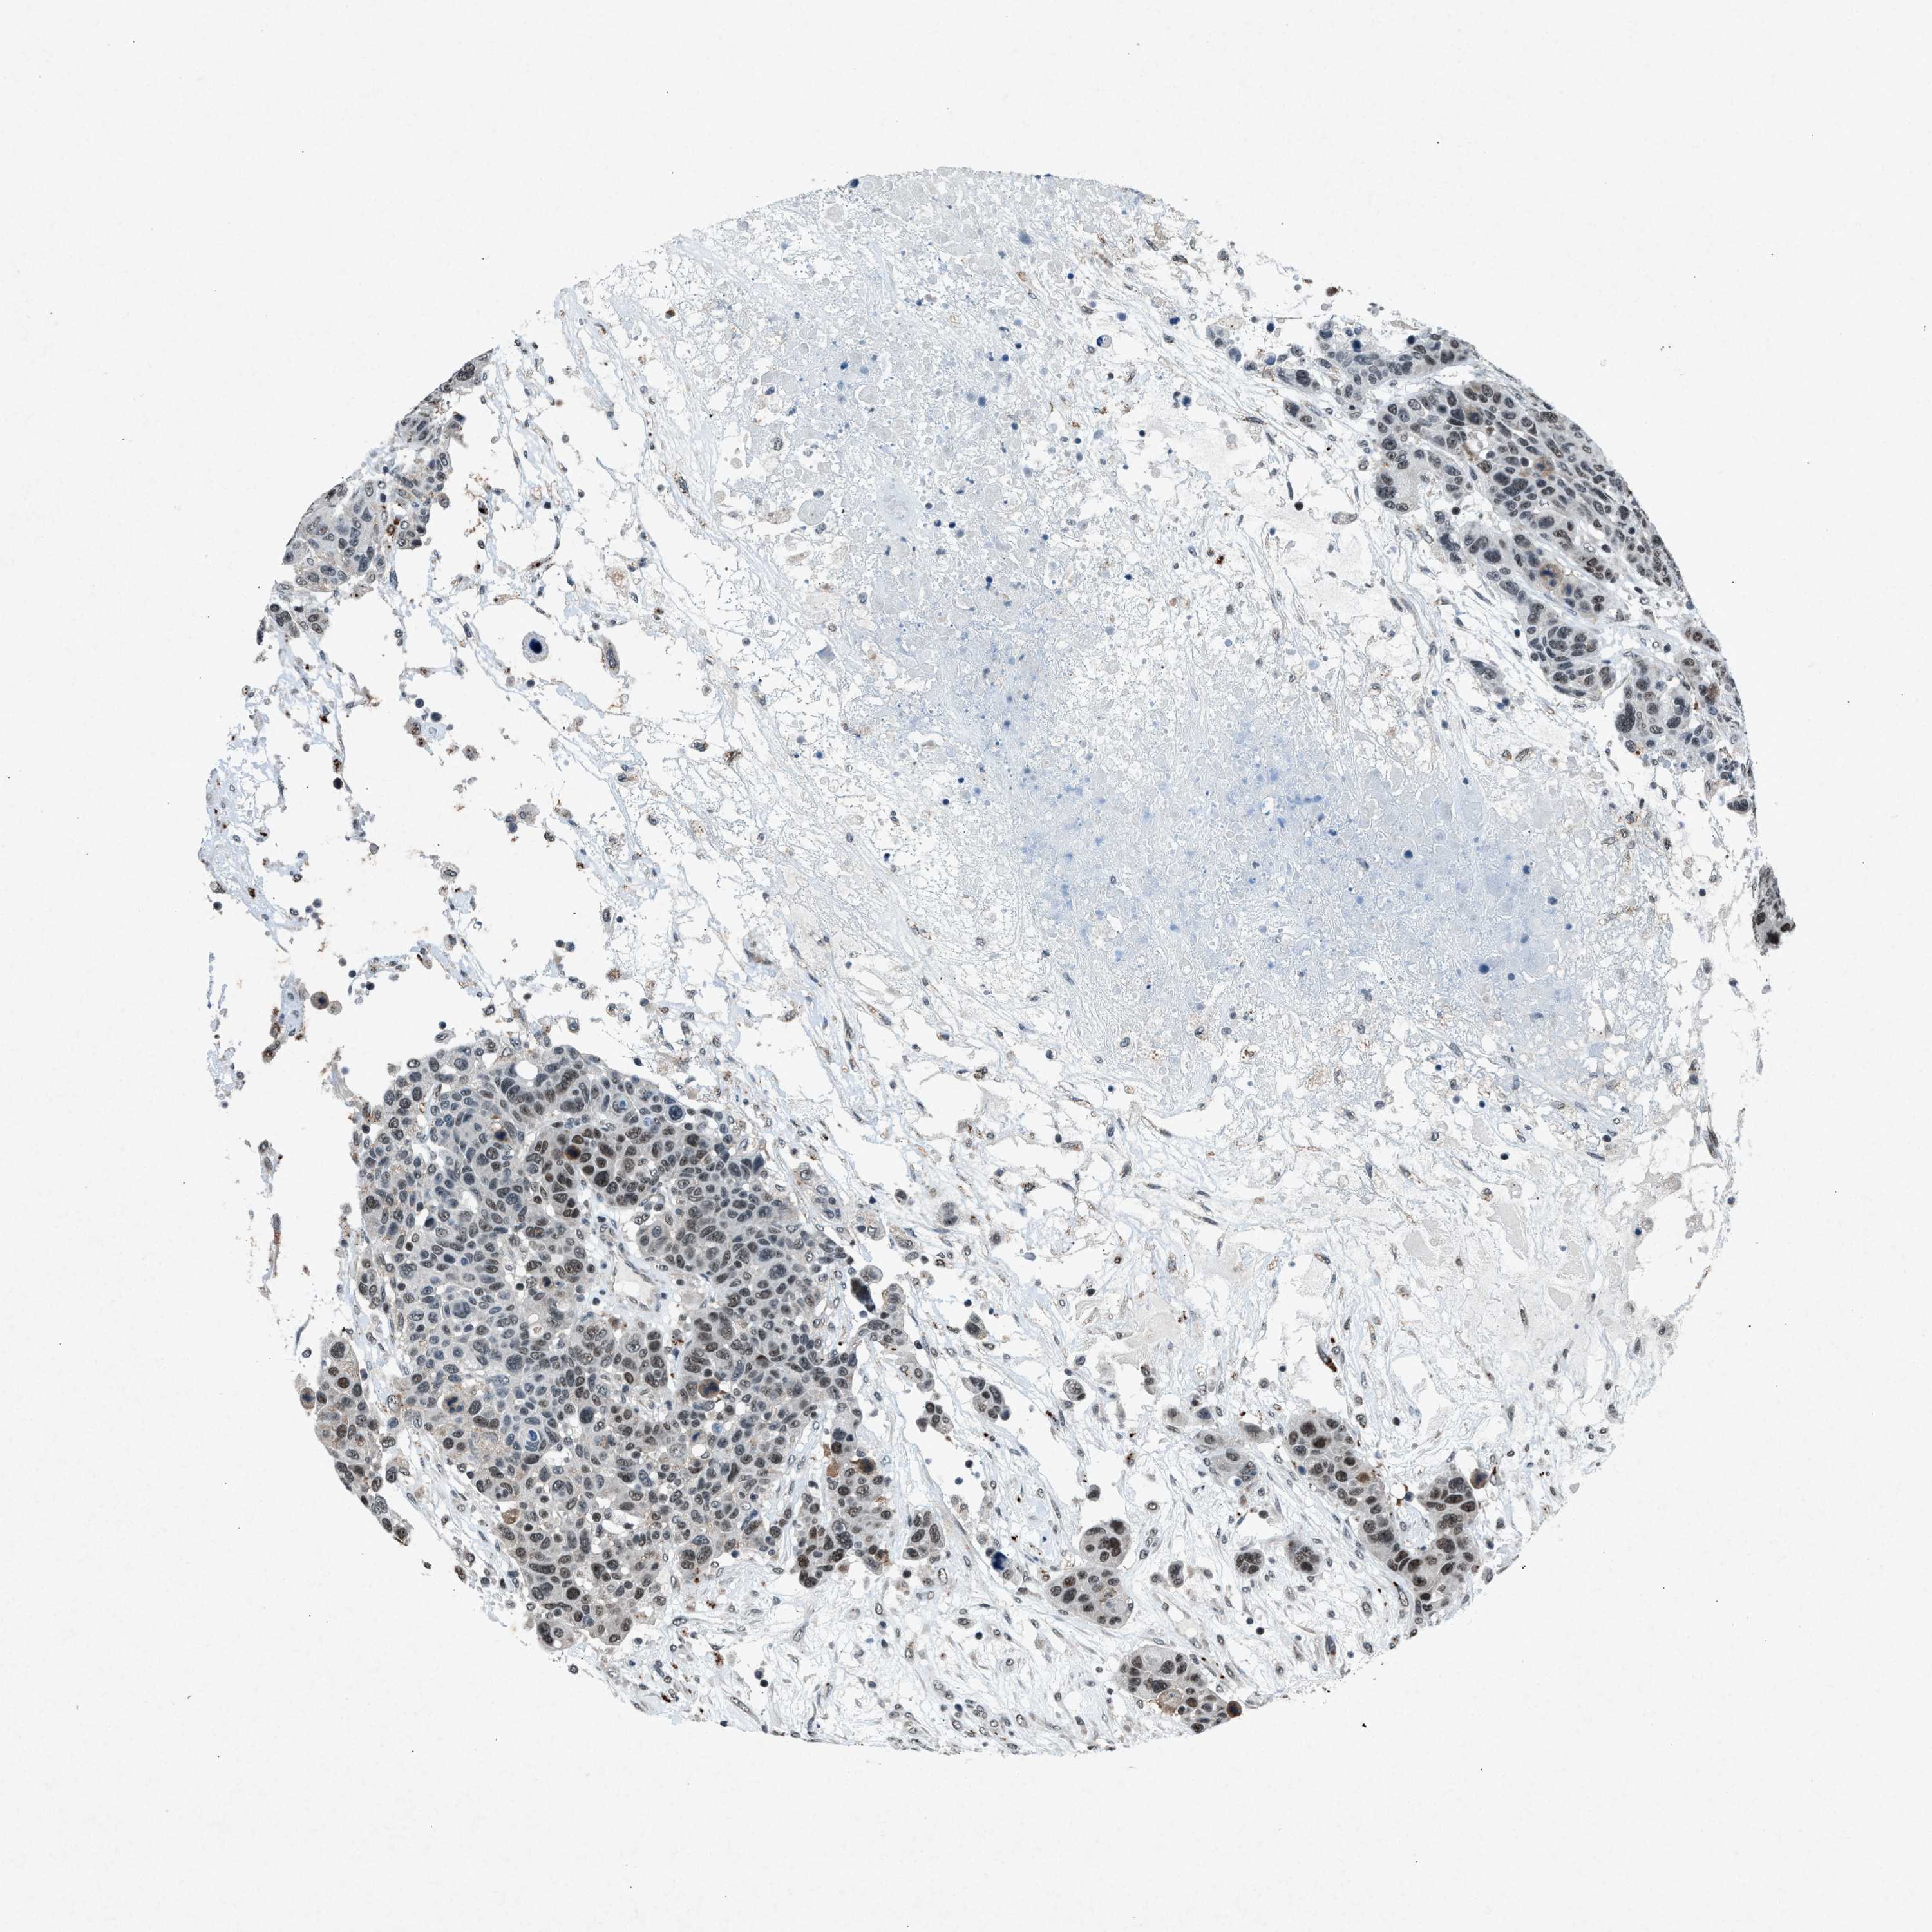

CANCER BREAST CANCER Show tissue menu

BRCA TCGA BRCA VALIDATION PROTEIN EXPRESSION